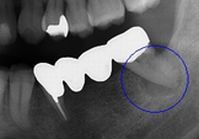

本日いらした50代男性の患者さま、初診は今から1年7か月前、下奥歯がズキズキ痛んで(左の写真;青い円)の来院でした。

その際にはお痛みの原因となっていた歯の根の治療の後、新しいブリッジを装着しました。本日はそのブリッジが外れていらしたのですが、それもそのはずです。このブリッジは仮着(仮止め)用のセメントで装着していました。

あんなにひどく痛み、レントゲン写真にも大きな影を認めた歯根の病変でしたので、しっかりとした根の治療と適切な機能(咬み合わせ)の回復及びブリッジ装着後のメンテナンスが必須です。

しかしながら患者さま曰く、当初のお痛みも消え去りブリッジもとても快適だったとのこと、仮止めのこともメンテナンスのこともすっかりお忘れのご様子でした。私たちの心配とは裏腹に、歯根の大きな病巣は良好な術後経過であることを知ることとなりました。